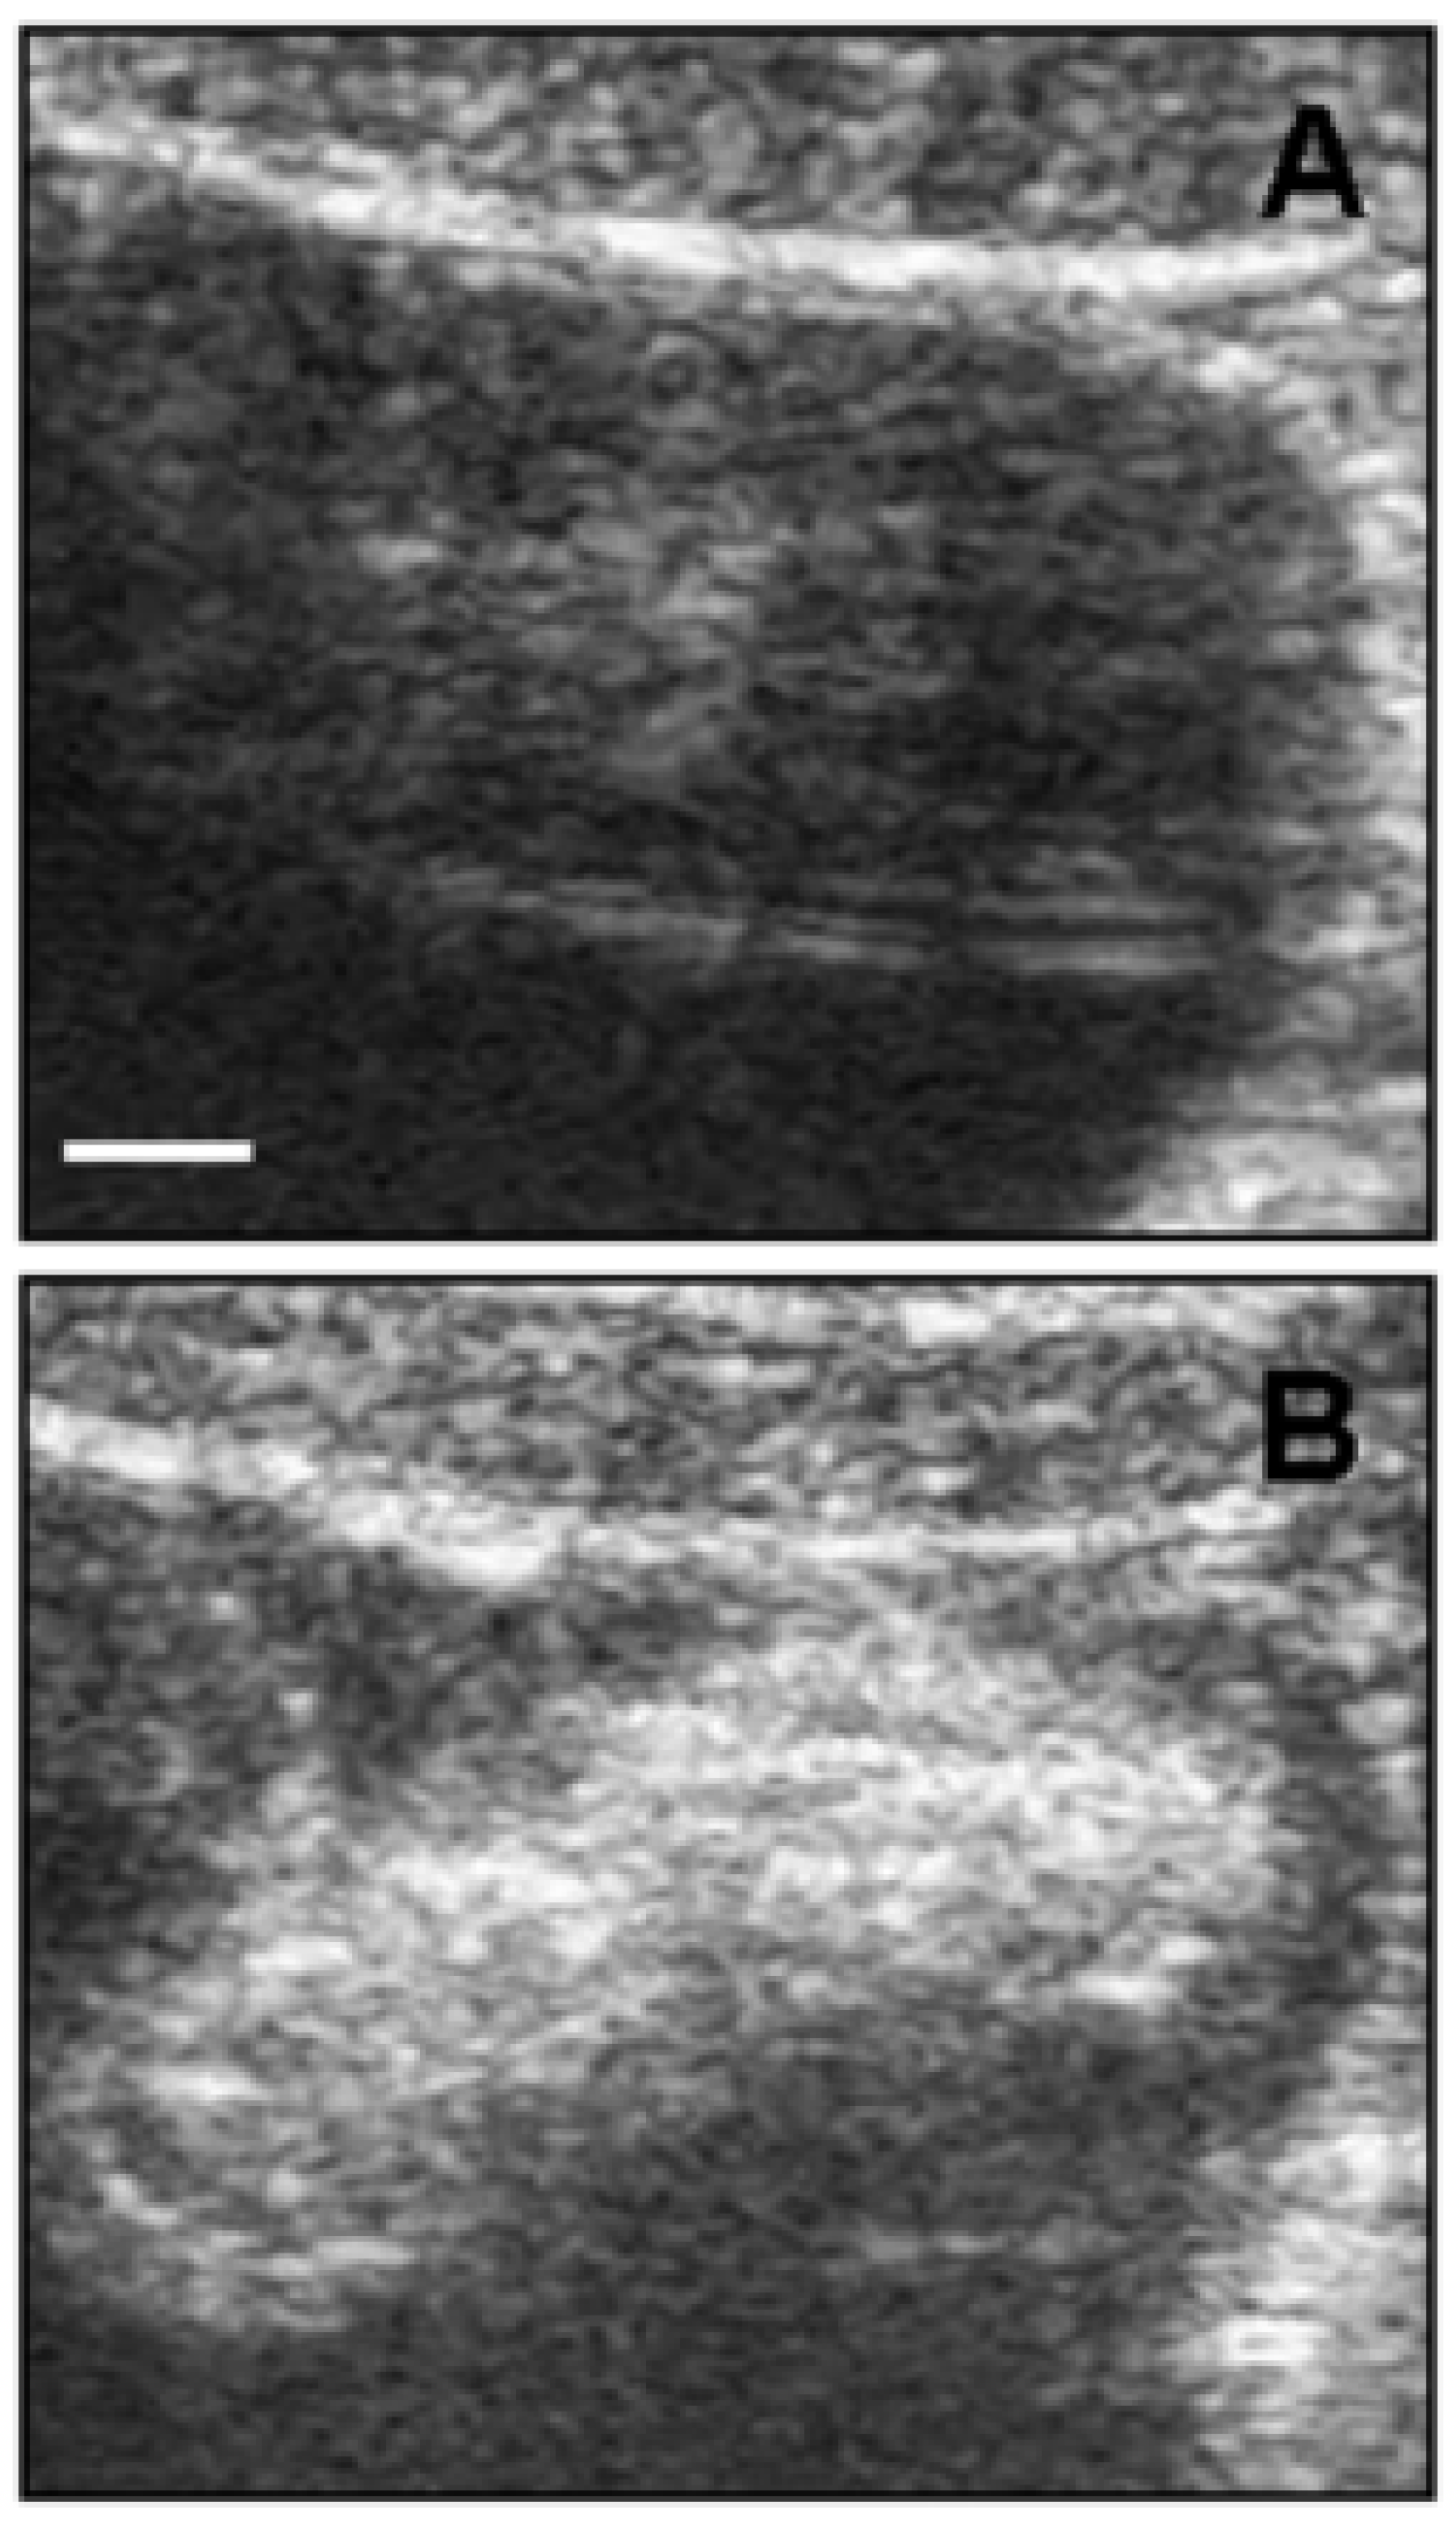

Another potential and emerging powerful use of CNTs is in the field of diagnostic imaging [50]. One of the most popular imaging techniques is ultrasonography due to the low price per examination and intrinsic safety [51]. The clinical application of UltraSound (US) involves sound waves in the range of 2 to 12 MHz, providing spatial resolution in the range 0.2 to 1 mm. Delogu et al. demonstrated the superior properties as ultrasound contrast agents of functionalized MWCNTs [52]. They functionalized MWCNTs with 1,3-dipolar cycloaddition of azomethine ylides (ox-MWCNT-NH3+) and compared with other kinds of carbon nanotubes, like pristine MWCNTs and functionalized SWCNTs, showing that the functionalized MWCNTs had a signal response comparable to a commercial contrast agent. They performed the test both in vitro and in vivo on a pig showing the validity of their approach (Figure 3).

Figure 3.

Ultrasound detection of functionalized MWCNTs in vivo. (A) Bladder ultrasound detection before ox-MWCNT-NH injection; (B) ox-MWCNT-NH were injected into the bladder. The images are representative results of two investigations in healthy pigs (scale bar, 5 mm). Reproduced from [52] with permission from the National Academy of Sciences of the United States of America.